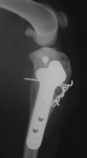

Cat versus car. This is so badly smashed that amputation would be a real option

Healing well and certainly good enough to be functional. Over the years bone remodelling will occur with use and the femur (thigh bone) will become more and more normal. Bones react to the pull of ligaments and muscle and weight bearing to become stronger and internal fixation (as opposed to a plaster cast) encourages early weight bearing and aids healing. This cat now walks normally